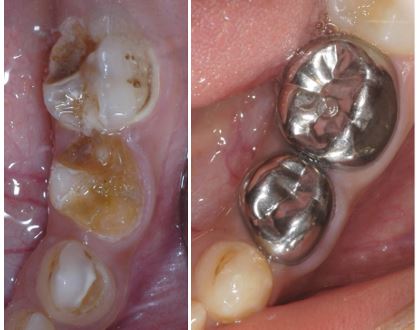

Phục Hồi Mão Thép Làm Sẵn Cho Răng Sữa

Răng sữa đóng vai trò quan trọng trong việc ăn nhai, phát âm và duy trì khoảng trống cho răng vĩnh viễn mọc lên. Tuy nhiên răng sữa có phần men răng và mô ngà...